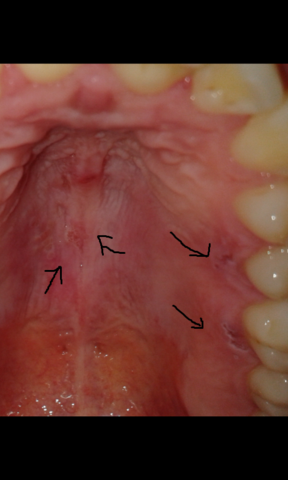

Offene stelle am gaumen. Sie haben ein zu hartes Brötchen mit Kanten und schon ist es passiert die Haut und weiteres Gewebe werden im Mundraum verletzt. Die Heizungsluft trocknet die Lippen aus mit der Zahnseide hat man sich das Zahnfleisch verletzt oder es kribbelt schon wieder ein Herpesbläschen eine kleine Wunde im Mund entsteht schnell. Einer Woche eine offene Stelle am Gaumen direkt hinter den Zähnen.

Offene stelle am gaumen hallo ich habe seit ca. Auf welche Symptome Sie achten sollten und mit welchen. Diese kann aufgrund von Verletzungen Infektionen allergischen Reaktionen oder gar Verbrennungen auftreten.

Diese wird genau untersucht. Eine Entzündung am Gaumen fällt meist durch eine schmerzhafte Schwelllung und Rötung auf. Beschwerden am gaumen bei zahnschmerzen hintergrund können zahnschmerzen sein die sich auf den gesamten mund rachen bereich ausdehnen und damit auch den gaumen betreffen können einleitung eine entzündung am gaumen fällt meist durch eine schmerzhafte schwelllung und rötung auf.